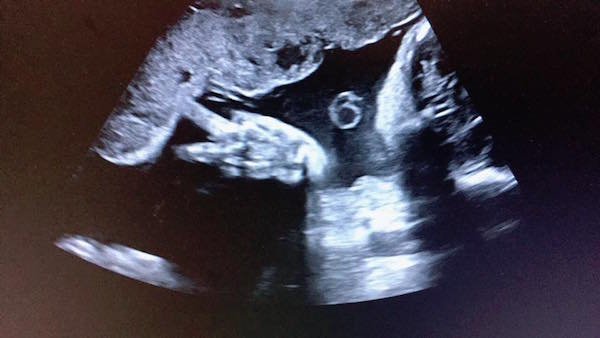

▼日前,嚴立婷去接受產檢,醫生卻告知她子宮頸變短,有早產跡象與危機,「現在Tammy才26週超級不適合出來,還有三個月才可以,小妞妳要乖好嗎!」

▼最近她有貼出女兒超音波照,顯示Tammy竟在裡面比出「YA」的手勢,崩潰失笑說:「媽咪每天嗑一堆藥辛苦安胎~妳在裡面倒是挺開薰的嘛!還有空比YA勒…算妳狠!」也附註Tammy已經有1300多公克,「給我乖乖待著,時間到了才准出來嘿!」